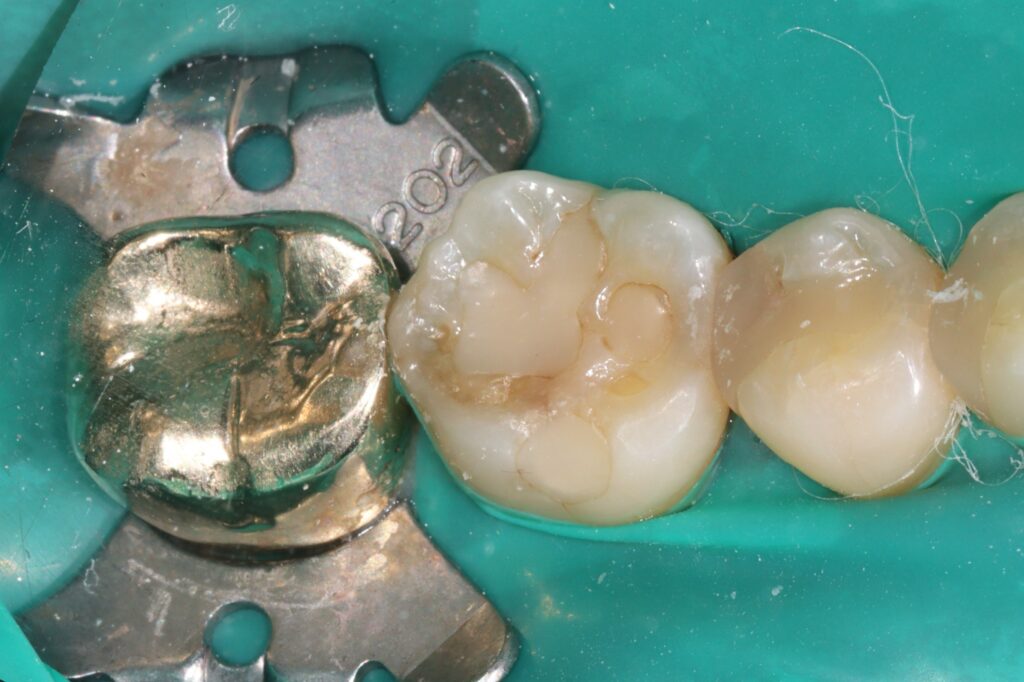

이번 증례에서는 구치부 치아의 손상으로 인해

레진 빌드업을 시행한 과정을 살펴보며,

치료 전 상태와 빌드업 과정,

그리고 회복된 결과를 중심으로

자세히 안내드리고자 합니다.

환자분께서는 아래쪽 어금니에 떼운 재료가

오래 되어 광화문치과에 내원해 주셨는데요.

손상된 부위를 정리한 뒤 접착 과정을 거쳐

복합레진을 여러 층으로 쌓아 올리며

치아 형태를 재구성하는 방식으로

진행되기 때문인데요.